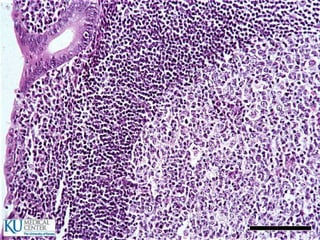

 El tercio posterior de la lengua tiene nódulos linfáticos

Lengua  El tercioposterior de la lengua tiene nódulos linfáticos  Criptas  Papilas:  Filiformes  Fungiformes  Circunvaladas  Foliadas